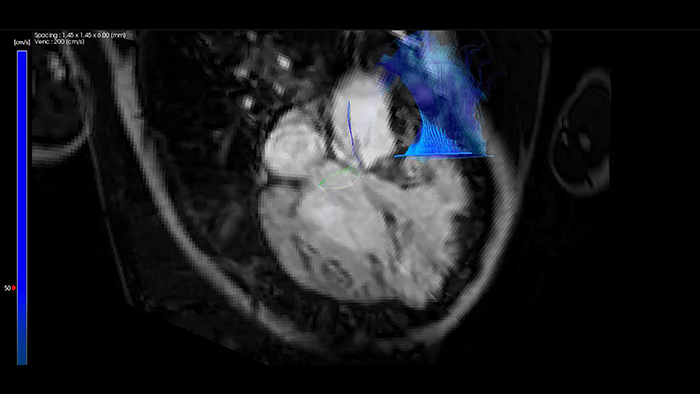

IntelliSpace Portal MR Caas 4D Flow em Tetralogia de Fallot

Orientação do stent de coartação aórtica com VesselNavigator